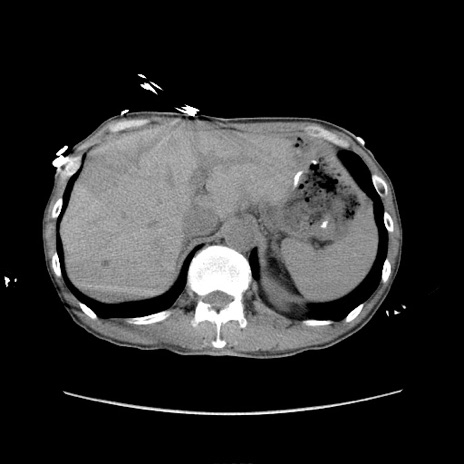

冠状断像

【症例】 60歳代男性

【主訴】 下腹部痛

【現病歴】 本日夜中より下腹部痛の症状認め、受診。

【既往歴】 膀胱癌(膀胱全摘+尿管皮膚瘻術) 、胃癌術後

【身体所見】 BT 35.3℃、PR 58/min、BP 136/98mHg、腹部平坦、軟、腸蠕動音±、ストマ留置あり、左上腹部~正中部に圧痛あり、反跳痛なし。

【データ】WBC 5100、CRP0.01